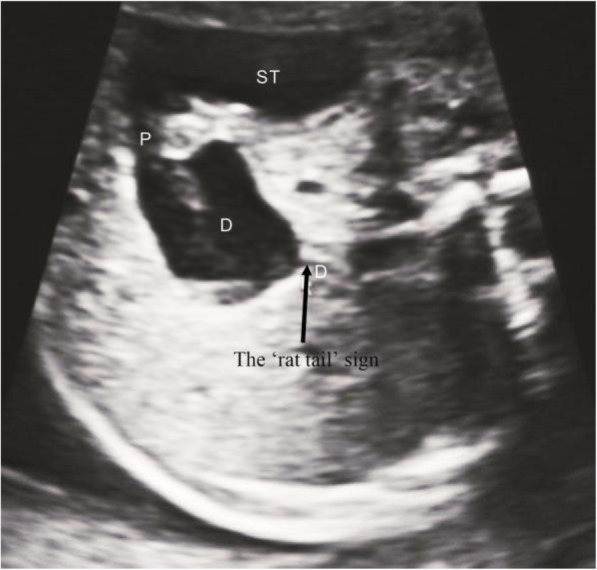

Continuous scanning along the dilated end of the duodenum (the lowest part of the diaphragm) showed empty intestines with low tension. The appearance on the ultrasound image resembled a rat tail. We called this ultrasound feature the ‘rat tail’ sign, as shown in Fig. 2.

The ‘rat tail’ sign (arrow), dilated end of duodenum and connected intestine from the transverse section of upper abdomen. Duodenum (D); Stomach (ST); Pylorus(P)

In this study, 21 patients with duodenal diaphragm were found, of whom 16 patients were confirmed by operation and anatomy, 5 patients were misdiagnosed. 1 patient was missed. The imaging feature of the ‘rat tail’ sign was found in all 17 patients. The specific analysis is shown below.

The diaphragm is a thin and transparent membrane structure that cannot be directly detected by ultrasound. However, it can be indirectly diagnosed by the ‘rat tail’ sign. The ‘rat tail’ sign was formed by the dilated intestine above the diaphragm and the empty intestine below the diaphragm. The diaphragm could occur in any part of the duodenum, especially near the ampulla of Vater. We found the diaphragm based on the anatomy of the patient, as shown in Fig. 3.

When the diaphragm was large, the stricture of the distal intestine led to the expansion of the duodenum above the diaphragm, showing a ‘wind bag’ shape. The intestine with little tension under the diaphragm presented a ‘rat tail’ sign, as shown in Fig. 4.